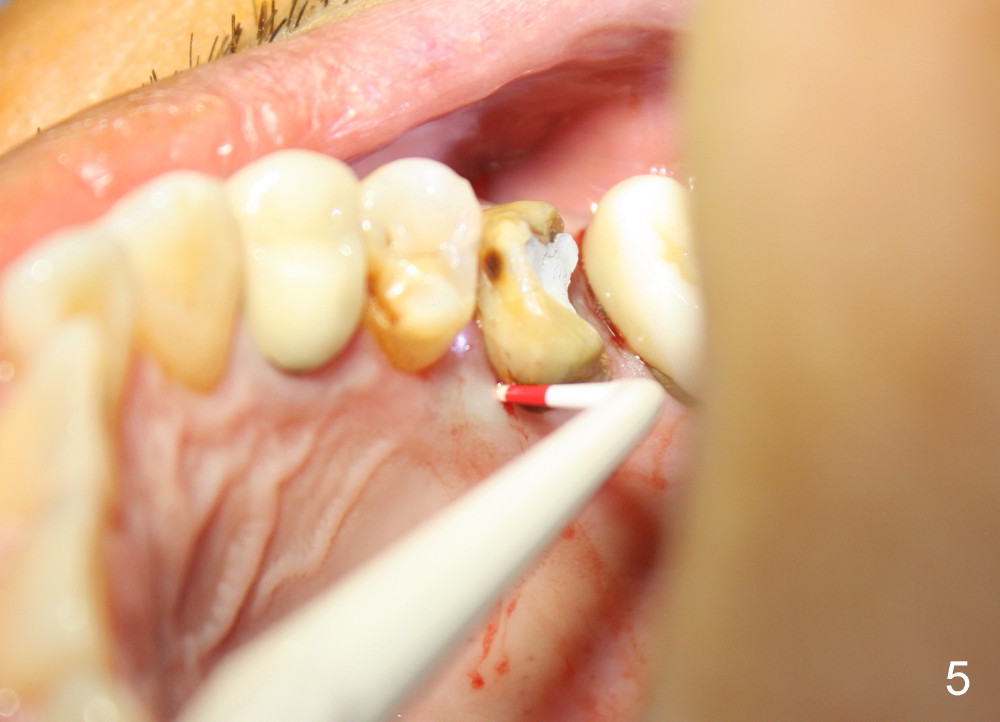

A 49-year-old man has multiple restoration (Fig.1). The tooth #14 appears to be non salvageable (Fig.2-6). The most interesting observation is that the sinus floor (Fig.1 ^) appears to be coronal to the tips of all three roots (mesiobuccal (MB), distobuccal (DB) and palatal (P)). This anatomic feature is confirmed by CBCT study (Fig.2). It will increase insertion torque of an implant to be placed if the sinus floor is raised among the root tips. That is, the apical portion of a large implant is engaged to the area among the apical portion of the three sockets. Let us use Fig.2 Coronal section for design of immediate implant with sinus lift. Click each figure for narrative.